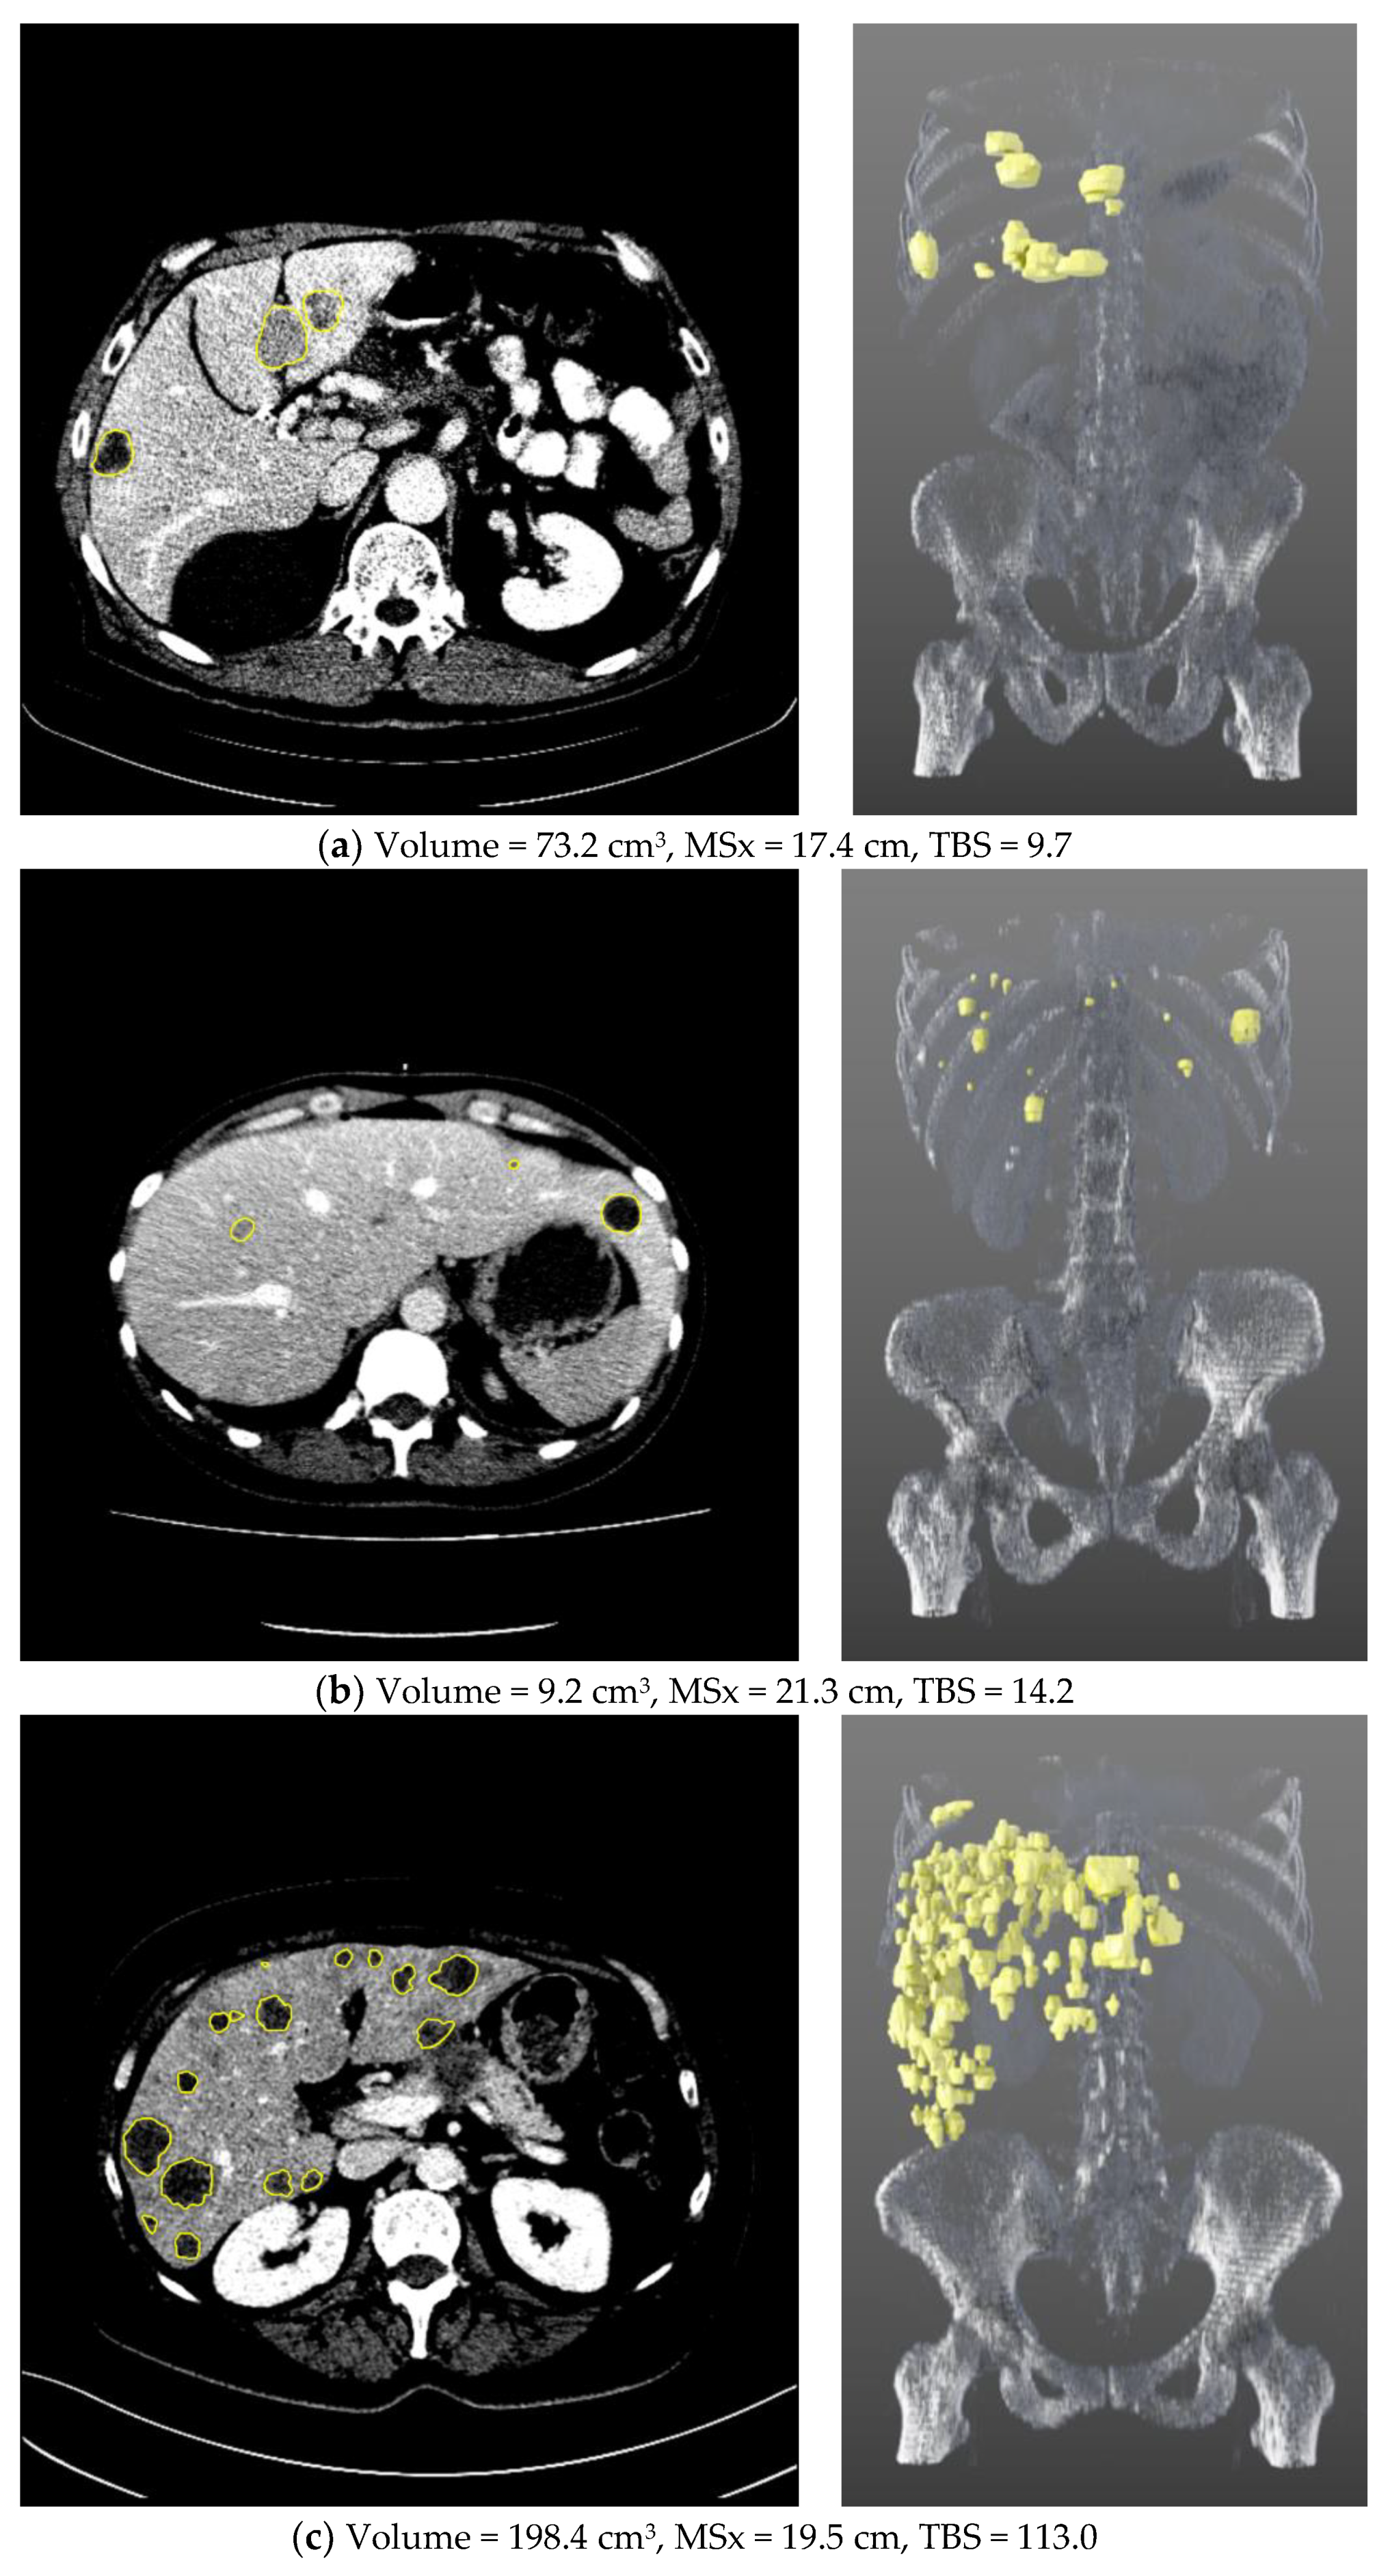

3.2. WLTB Segmentations